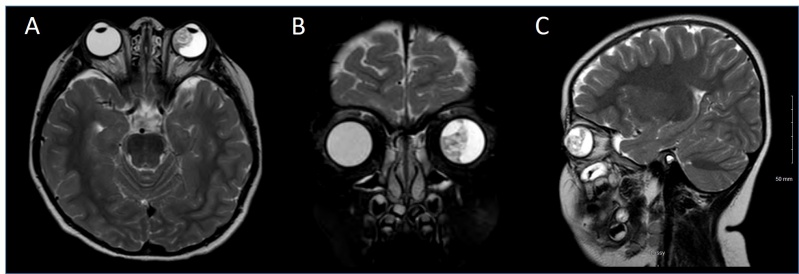

Figure 7: T2 MRI Images of a patient with A) Axial, B) Coronal and C) Sagittal sections showing an irregular soft tissue lesion within the left globe occupying nearly half of the vitreous region. The lesion is of mixed signal intensity. No obvious macroscopic retrobulbar extension is visualized.